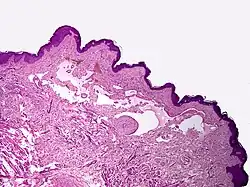

Proliferating lymphangioma, H&E stain. Sometimes endothelial cells begin to divide excessively.

In 1976, Whimster studied the pathogenesis of lymphangioma circumscriptum, finding lymphatic cisterns in the deep subcutaneous plane are separated from the normal network of lymph vessels. They communicate with the superficial lymph vesicles through vertical, dilated lymph channels. Whimster theorized the cisterns might come from a primitive lymph sac that failed to connect with the rest of the lymphatic system during embryonic development.

A thick coat of muscle fibers that cause rhythmic contractions line the sequestered primitive sacs. Rhythmic contractions increase the intramural pressure, causing dilated channels to come from the walls of the cisterns toward the skin. He suggested that the vesicles seen in lymphangioma circumscriptum are outpouchings of these dilated projecting vessels. Lymphatic and radiographic studies support Whimsters observations. Such studies reveal that big cisterns extend deeply into the skin and beyond the clinical lesions. Lymphangiomas that are deep in the dermis show no evidence of communication with the regular lymphatics. The cause for the failure of lymph sacs to connect with the lymphatic system is not known.[7]

Microscopically, the vesicles in lymphangioma circumscriptum are greatly dilated lymph channels that cause the papillary dermis to expand. They may be associated with acanthosis and hyperkeratosis. There are many channels in the upper dermis which often extend to the subcutis (the deeper layer of the dermis, containing mostly fat and connective tissue). The deeper vessels have large calibers with thick walls which contain smooth muscle. The lumen is filled with lymphatic fluid, but often contains red blood cells, lymphocytes, macrophages, and neutrophils. The channels are lined with flat endothelial cells. The interstitium has many lymphoid cells and shows evidence of fibroplasia (the formation of fibrous tissue). Nodules (A small mass of tissue or aggregation of cells) in cavernous lymphangioma are large, irregular channels in the reticular dermis and subcutaneous tissue that are lined by a single layer of endothelial cells. Also an incomplete layer of smooth muscle also lines the walls of these channels. The stroma consists of loose connective tissue with a lot of inflammatory cells. These tumors usually penetrate muscle. Cystic hygroma is indistinguishable from cavernous lymphangiomas on histology.[7]